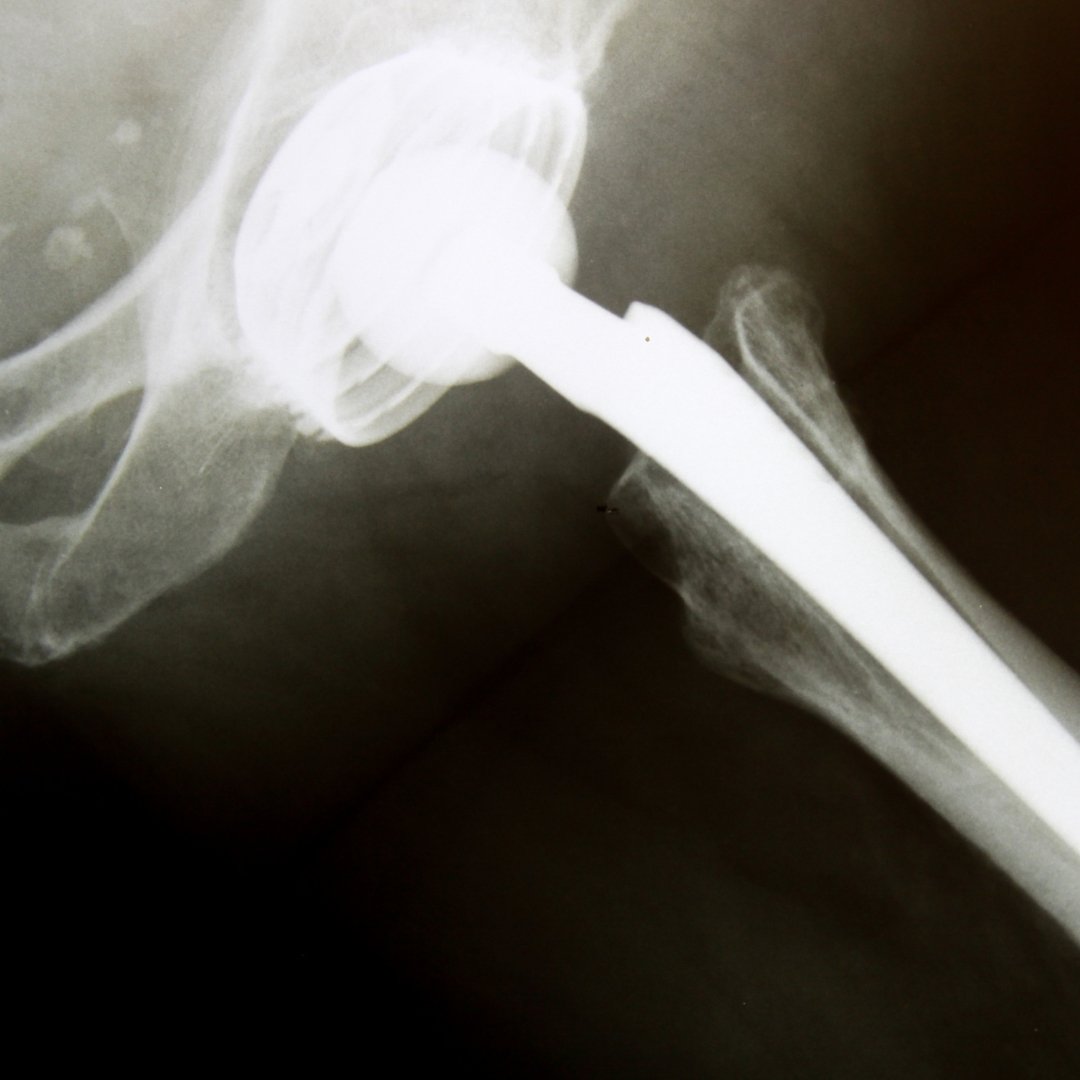

Ендопротезування — це хірургічне втручання, під час якого зруйнований або деформований суглоб частково чи повністю замінюють штучним імплантом — ендопротезом. Він повторює анатомічну форму суглоба та дозволяє відновити його функцію.

Сучасні ендопротези виготовляються з біосумісних матеріалів, добре приживаються в організмі та розраховані на тривалий термін служби.

– кульшового (тазостегнового) суглоба